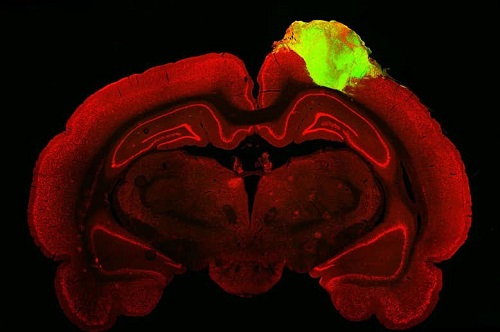

小鼠大脑(红色)与植入的人脑类器官(绿色).